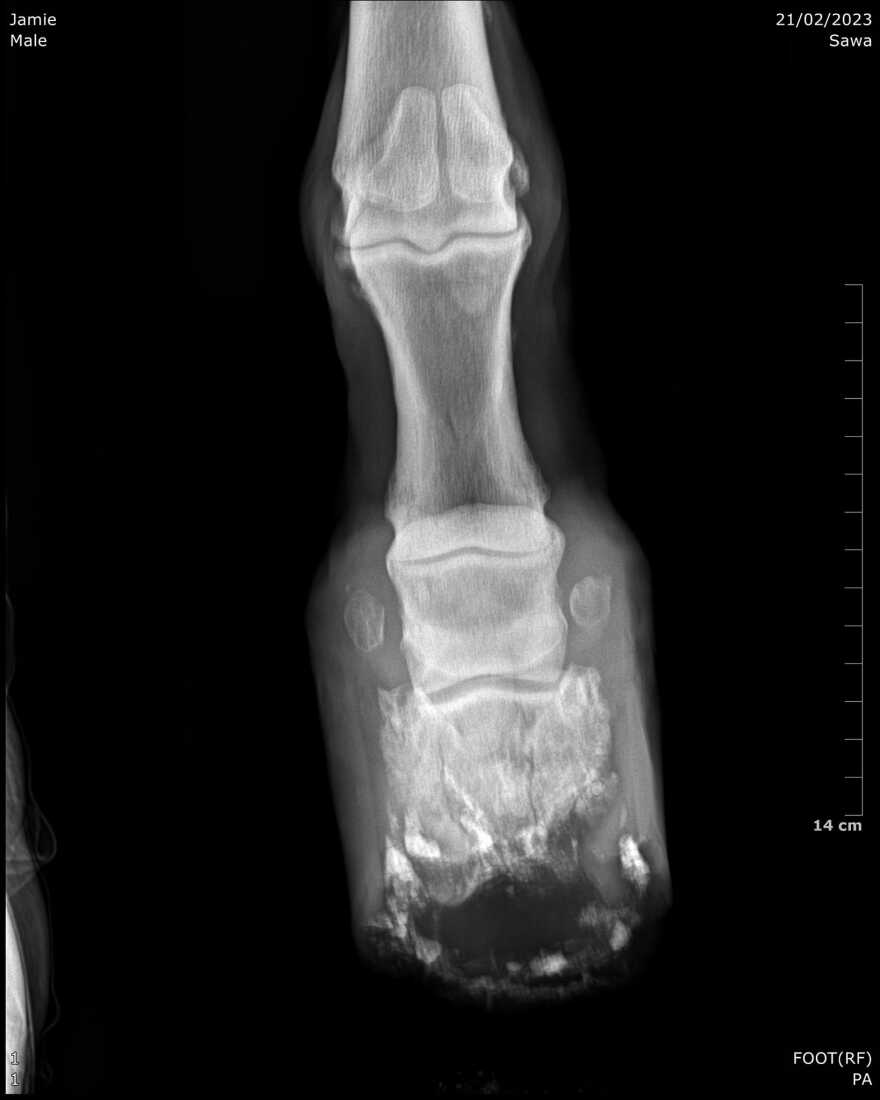

Τελικά καταφέραμε να στήσουμε την αποστολή να έρθει αεροπορικώς ένας διακεκριμένος κτηνίατρος ιπποειδών από τη Θεσσαλονίκη με το φορητό ακτινολογικό του μηχάνημα για μια ολόκληρη μέρα. Πάνω από 10 από τα γαϊδουράκια με τις χειρότερες περιπτώσεις ακτινογραφήθηκαν για πρώτη φορά στη ζωή τους... Οι εικόνες αυτές έλεγαν τις ιστορίες τους, απαντούσαν σε ερωτήματα που δεν μπορούσαμε ποτέ πριν να εξηγήσουμε, αποκάλυπταν το σπαρακτικό τίμημα της καταπονημένης ζωής τους και σε πολλές περιπτώσεις την απολύτως απαράδεκτη λανθασμένη χρήση αυτών των ζώων που η φύση τους τα κρατάει να δουλεύουν- κυριολεκτικά- μέχρι να αφήσουν την τελευταία τους πνοή.

Μακράν η πιο θλιβερή διάγνωση ήταν αυτή του Τζέιμι, ο οποίος δεν είναι μια συνηθισμένη ράτσα στην Ελλάδα και το σώμα του δεν είναι καθόλου σχεδιασμένο να αντέξει το διάβα των 588 σκαλοπατιών στο παλιό λιμάνι ούτε το βάρος των οικοδομικών υλικών που έσερνε στα βράχια της Καλντέρας... Με απέραντη θλίψη του είπαμε χθες το τελευταίο αντίο και ο κτηνίατρός μας τον βοήθησε να φύγει από τη γη χωρίς άλλους πόνους. Σε μια φωτογραφία που είναι ίσως η πιο δύσκολη να την κοιτάξεις βλέπεις τους φίλους του να τον ακολουθούν καθώς τον παίρναμε για ταφή.